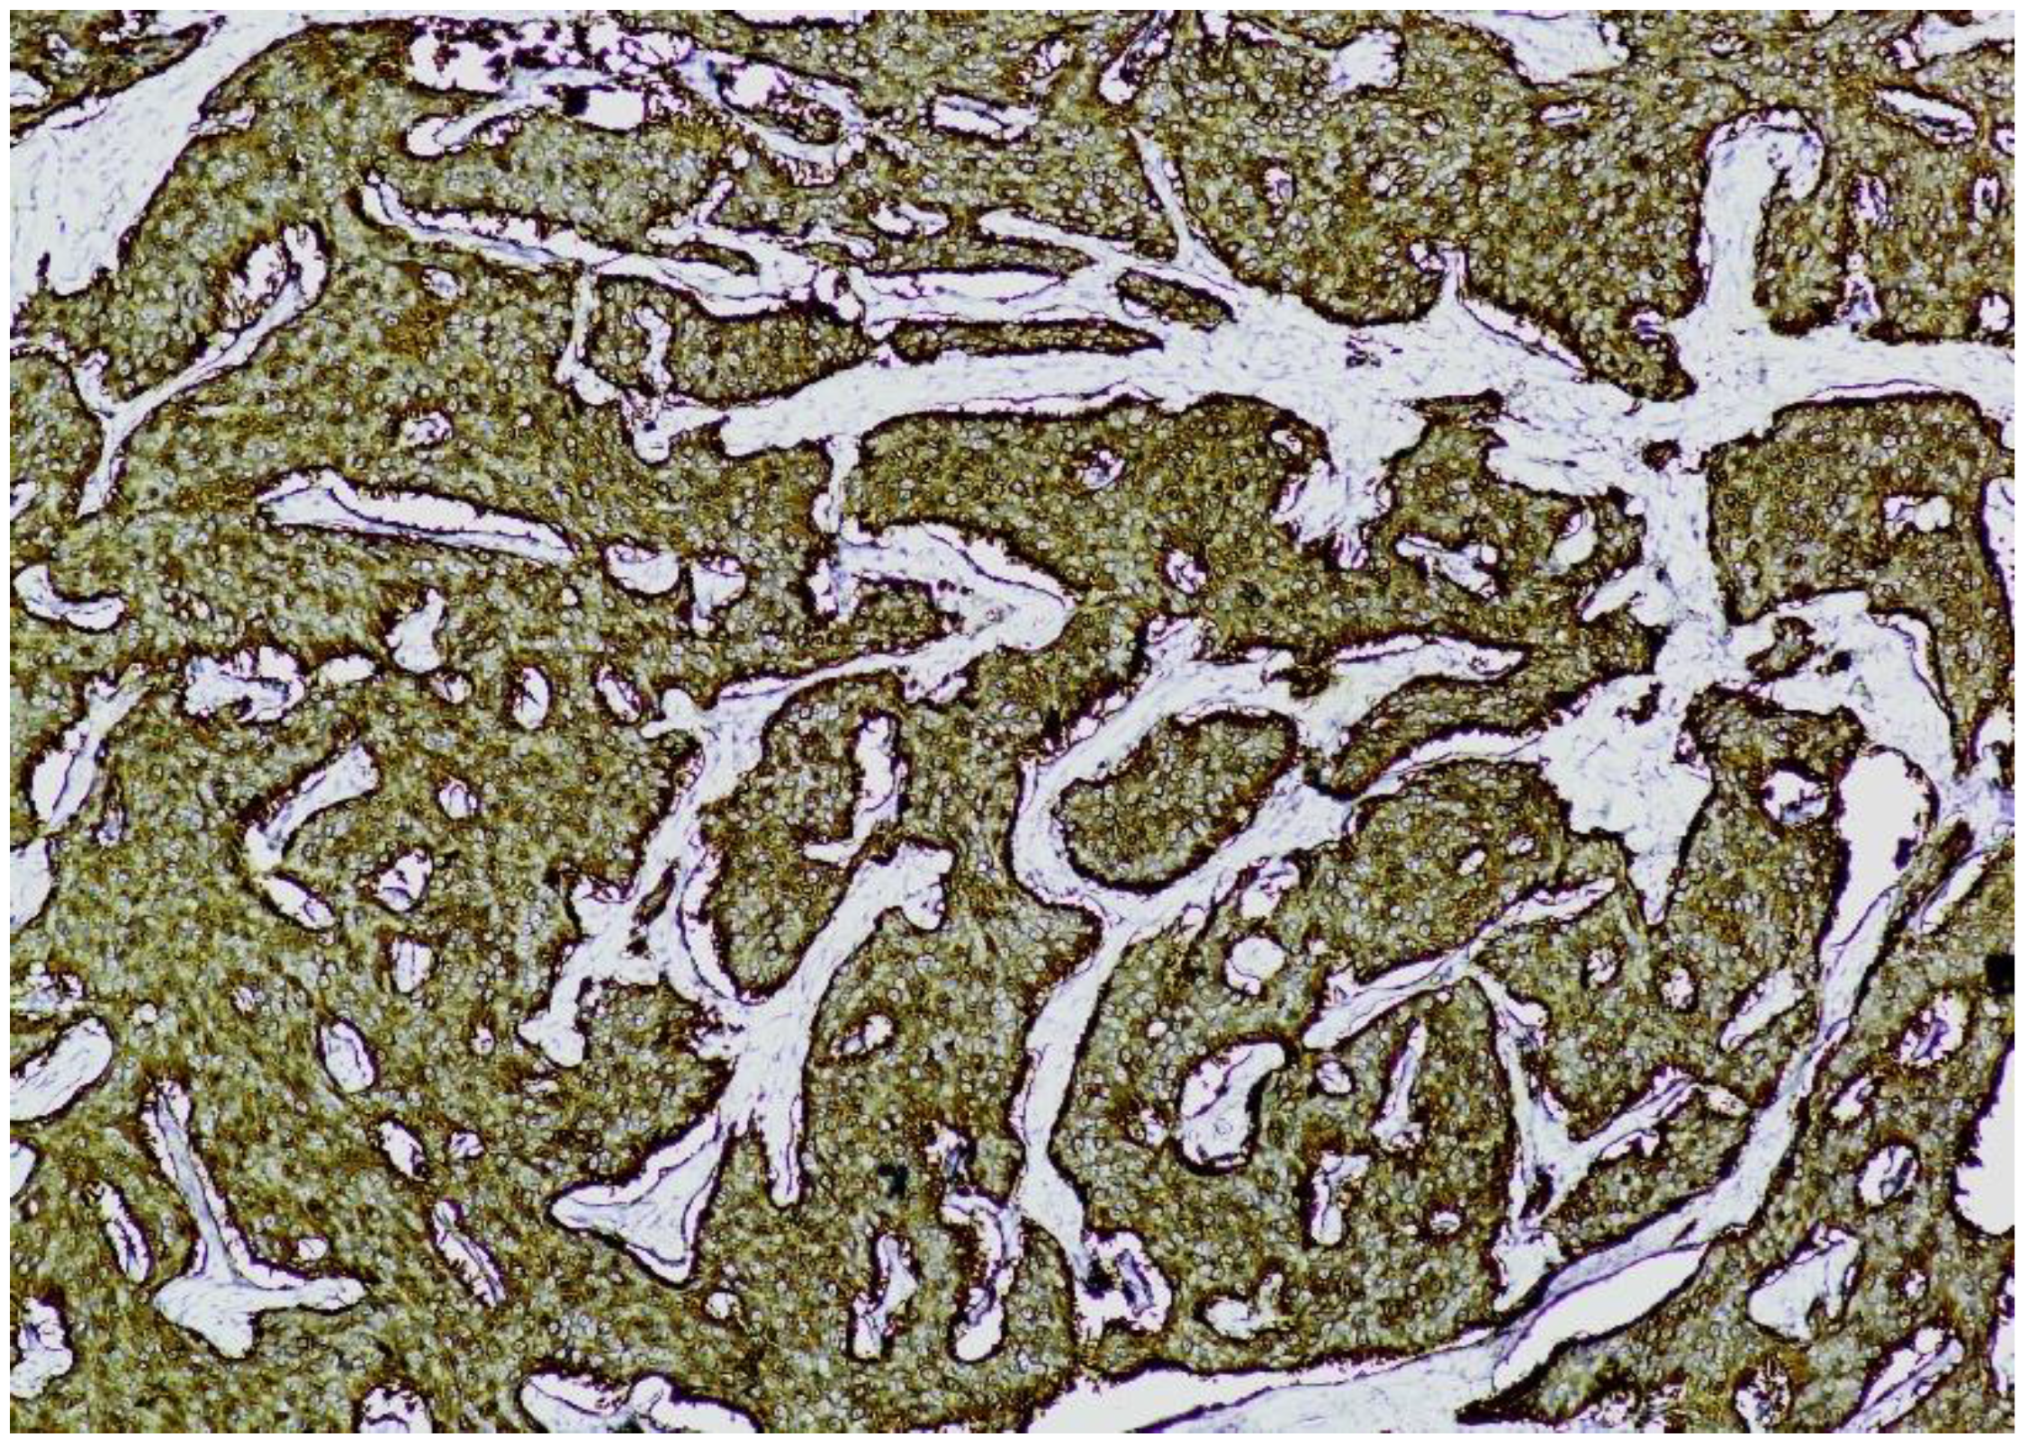

Immunohistochemistry (IHC) showed diffuse and strong positivity for chromogranin A and CD56, with focal weak staining for synaptophysin, supporting neuroendocrine differentiation (Figure 5, Figure 6, Figure 7 and Figure 8).

Figure 5. Chromogranin A immunostaining (×100). Diffuse and strong cytoplasmic staining is observed in nests of uniform neuroendocrine tumor cells, confirming neuroendocrine differentiation.